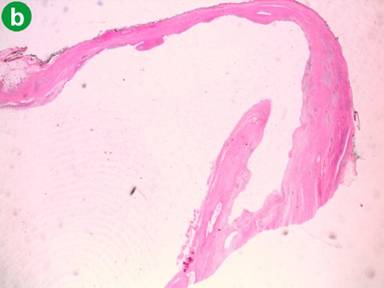

With these findings, because the patient had no a history of pancreatitis and considering the age, the sex and the imaging characteristics, a presumptive diagnosis of cystic neoplasm of the pancreas was made and a first hypothesis of a mucinous cystadenoma of the pancreatic tail was performed. A distal pancreatectomy with total splenectomy was performed. On gross inspection the pancreatic tail hosted a cyst with a smooth surface, 9 cm of maximum diameter, bilocular, containing a brownish liquid; furthermore, the lesion was adherent to the splenic capsule. Microscopically a fibrous cystic wall lined by a monolayer of cuboid epithelial cells without evidence of malignancy allowing the diagnosis of true pancreatic cyst (Figure 5). The post-operative course was uneventful and the patient was discharged 7 days after surgery; at 3-year follow-up, the patient is alive without evidence of recurrence.

Figure 5. a. Fibrous wall of the pancreatic cyst lined by cuboidal epithelium monolayer (green arrow) with trapped Langerhans islets (yellow arrows) (H&E, 10x); b. Cross section compared to the septum of the cyst (H&E, 1x).